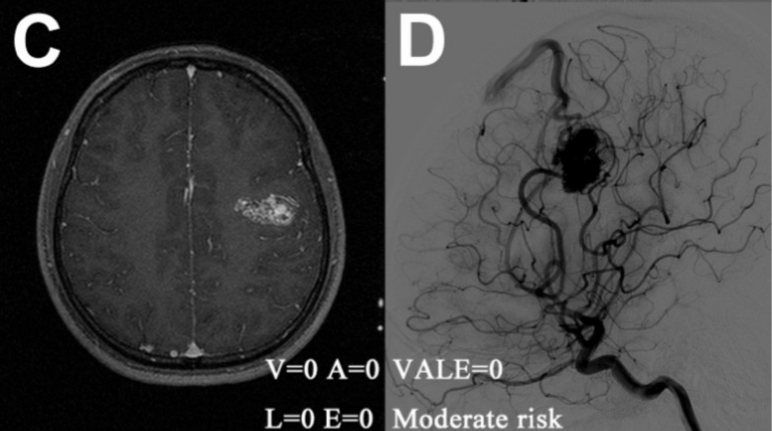

典型案例:A-B,1例伴有癫痫的未破裂AVM患者,通过VALE模型(脑室系统受累= 0,静脉瘤= -4,深部位置= 0,单一深静脉引流= 0,VALE= -4)评估为低危组,诊断后8.75年内随访无出血(静脉瘤:绿色箭头);

典型案例:C-D,1例以钝性头痛为表现的未破裂AVM患者,经VALE模型评定为中危组(脑室系统受累= 0,静脉瘤= 0,深部位置= 0,单一深静脉引流= 0,VALE= 0),诊断后随访6.25年无出血;